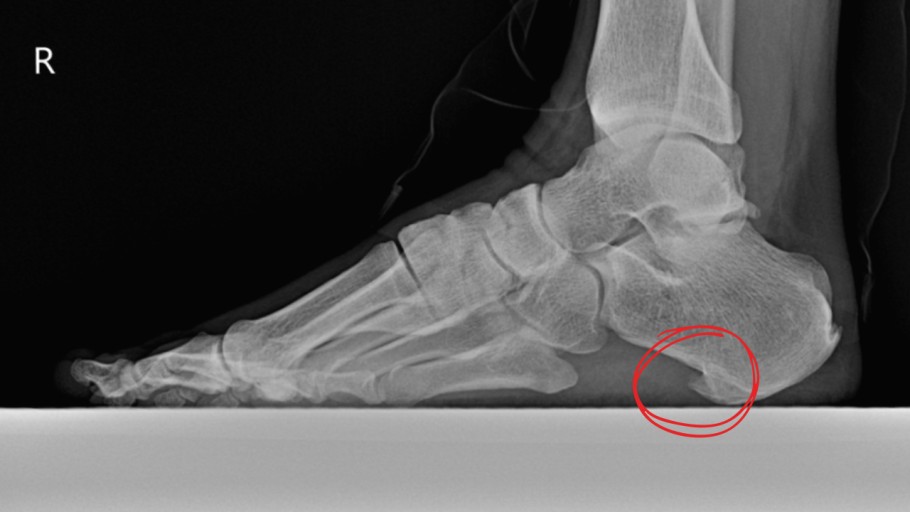

족저 근막염 증상 2. 발뒤꿈치 중앙 통증

- 발뒤꿈치 중간 또는 안쪽이 찌릿하거나 쑤시는 듯한 통증

- 눌렀을 때 통증이 더 심해지는 경우 많음